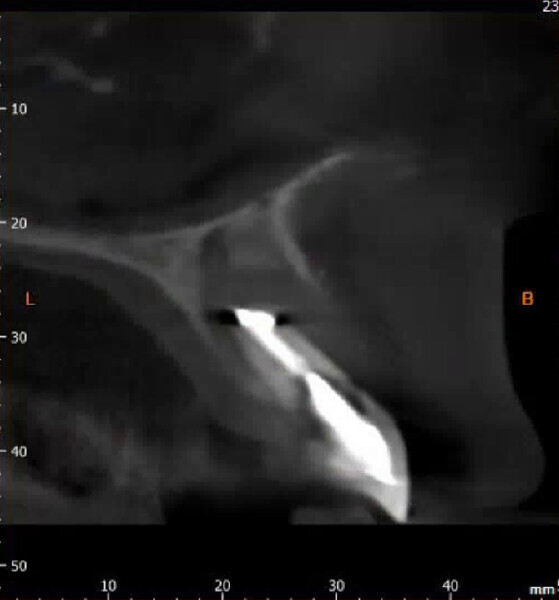

Fig. 15: Verification jig locked in situ to gain implant passivity.